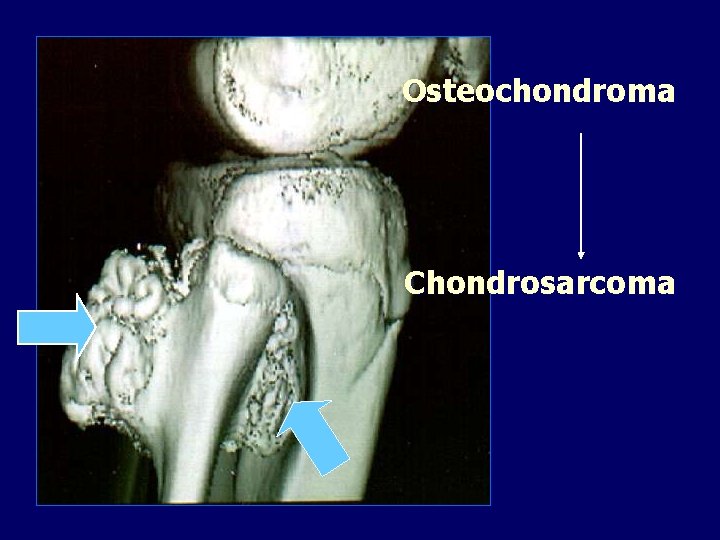

Osteochondroma Chondrosarcoma

Malignant transformation Usually occurs above the age of 40 years. Sudden increase in size. Swelling becomes painful.